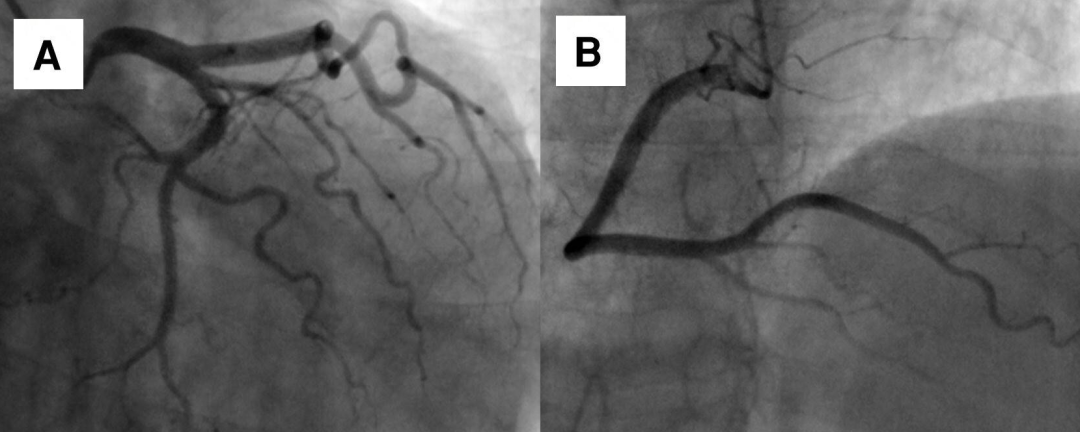

患者女性,69岁,因体检心电图发现T波改变,到心脏科就诊。患者既往无心脏相关病史及心血管危险因素。超声心动图检查发现室间隔肌部瘤样膨出,未发现左向右分流。冠状动脉造影证实冠状动脉正常。左心室造影可见室间隔肌部瘤形成。进一步行心脏CTA及MRI检查,结果显示巨大室间隔肌部瘤,直径与胸主动脉直径相当,未见血栓形成。鉴于患者无症状且无血流动力学影响,采取保守治疗策略,包括生活方式干预、定期心脏监测及规律随访。虽考虑预防性抗凝治疗可能会获益,但由于无血栓形成、血流动力学稳定且缺乏其他危险因素,最终未予实施。不抗凝虽可能增加血栓形成风险,但瘤体内的血流状态可能减少了血栓形成机会,避免了抗栓治疗相关的出血风险。嘱患者每6个月复查超声心动图,必要时行MRI检查。随访期间患者持续无症状且无新发异常,故继续维持原监测方案。

图为心电图、冠状动脉造影、经胸超声心动图、CTA及MRI检查结果。心电图显示v2-4导联T波改变(图A)。左心室造影可见室间隔肌部瘤(图C)。超声心动图显示室间隔瘤样结构(图D)。CTA与MRI均显示巨大室间隔肌部瘤(图E、F)。